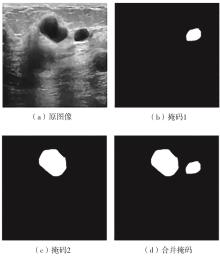

乳腺癌是全球女性最常见的恶性肿瘤之一,准确的病变分割对于乳腺癌的早期诊断与治疗具有重要意义。然而,由于病变形态的多样性以及超声成像机制的复杂性,现有基于深度学习的乳腺超声图像病变分割方法在分割准确性方面仍面临巨大挑战。为进一步提升乳腺超声图像中病变区域的分割精度,该文基于经典U-Net架构,提出了一种新型乳腺超声图像病变分割网络(CWSASKM-BBAM-Net)。首先,在网络中引入逐通道空间自适应选择核卷积模块(CWSASKM),根据不同通道的语义特征为每个空间位置自适应选择感受野大小,以增强多尺度信息的建模能力;然后,引入双向边界感知机制(BBAM),通过融合正向与反向注意力,对目标显著区域及其边界进行协同建模,同时逐步提升对非显著区域与病变区域的区分能力,以进一步强化边界信息的表达;最后,在3组公开乳腺超声图像数据集(BUSI、UDIAT和STU)上开展分割实验。结果表明:该方法在数据集BUSI上的杰卡德指数、精确率、召回率和Dice相似系数分别为71.97%、82.85%、81.40%和80.44%,较次优方法分别提升1.69、1.05、1.28和1.84个百分点;在数据集UDIAT上,这4项指标分别达到78.14%、88.31%、86.73%和86.10%,较次优方法分别提升了2.75、2.04、0.56和2.01个百分点;在外部数据集STU上,该方法也取得了优于其他方法的整体表现。实验结果表明,CWSASKM-BBAM-Net在乳腺超声图像分割任务中展现出更优的整体性能。